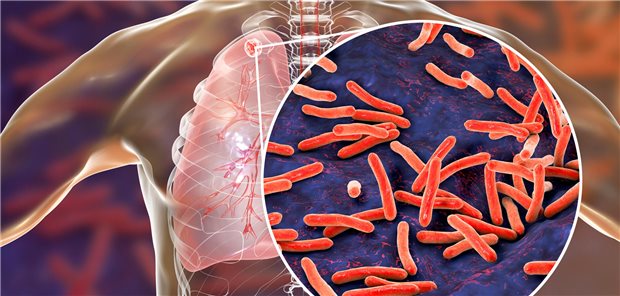

Unterfinanzierung des NHS leistet Ausbreitung Vorschub

Zahl der Tuberkulose-Infektionen in Großbritannien nimmt zu